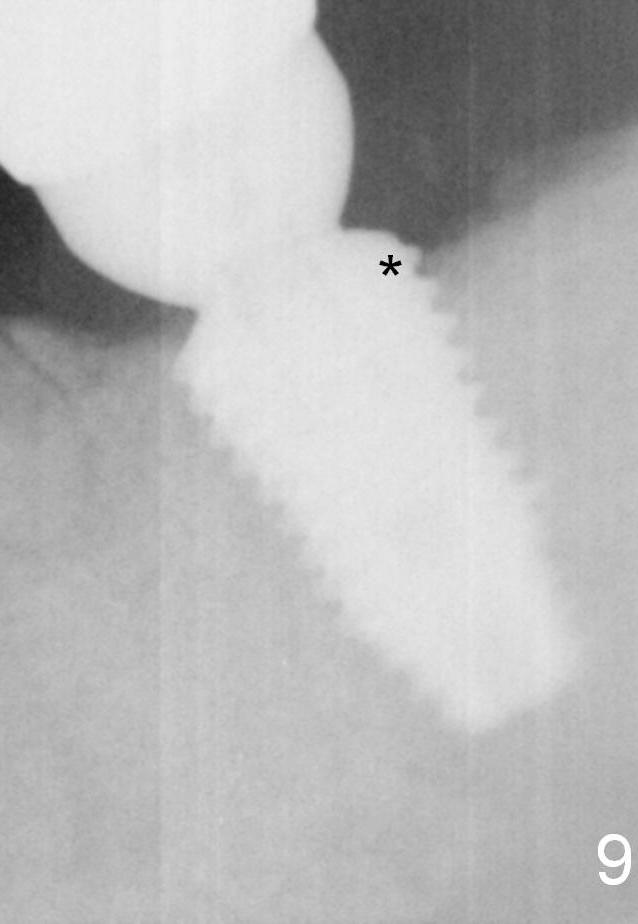

Eight months post cementation (1 year postop), the patient is pleased with the implant crown (Fig.9). One distal thread appears not covered by the bone (*). The implant should have been placed a little deeper or a smaller implant should have been used.